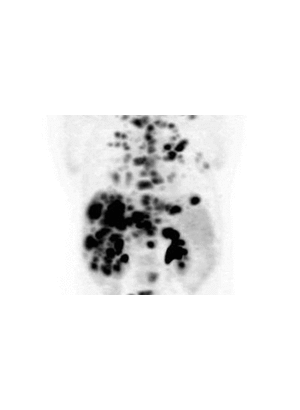

(VTC News) - Sau một thời gian dài chiến đấu với căn bệnh ung thư hạch bạch huyết hiếm gặp, người đàn ông Mỹ này đã may mắn khỏi bệnh nhờ một loại thuốc mới có khả năng làm tiêu biến khối u ác tính.